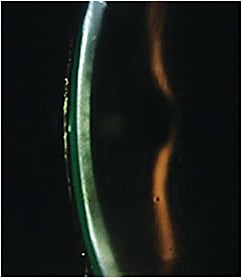

- Signs and Symptoms Gradually decreased vision with glare and halos often occurs with increased lens wear. Vision improves minimally even with lens removal and reapplication and may persist for several hours after lens wear. A hazy or thickened cornea can be observed with biomicroscopy (Figure 4) or global pachymetry. Patients who have a compromised endothelial cell count of 800 cells/mm2 or less are at the greatest risk of developing corneal edema with scleral lens wear (Fadel and Kramer, 2019).

Figure 4. Corneal haze can be seen behind the tear lens reservoir in a patient who has Fuchs’ dystrophy. - Treatment and Management Optimize oxygen transmission by utilizing high-Dk materials, keeping the tear reservoir and lens center as thin as possible, and increasing tear exchange with lens fenestrations (Ezekiel, 1983). Some patients may only tolerate intermittent lens wear for short periods of time to prevent corneal exhaustion. Topical hyperosmotic drops or ointments before and after lens wear can facilitate fluid regulation. It is important to stress the dangers of long-term corneal edema with patients, as it can lead to permanent vision loss or transplant failure.